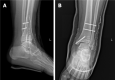

Case summary: A 16-year-old patient sustained left medial malleolar fracture, and the associated inferior tibiofibular syndesmotic instability was overlooked. After open reduction and internal fixation of the medial malleolar fracture, inferior tibiofibular syndesmosis diastasis with IOM rupture was detected by auxiliary imaging. Secondary surgical intervention was performed to reduce anatomically and fix with two trans-syndesmosis screws. Twelve weeks later, the screws were removed. At the 6-mo follow-up, the patient gained full range of motion of the ankle.

Conclusion: Complete syndesmosis injury with IOM rupture should be considered Maisonneuve-type injury. Open reduction and internal fixation could obtain good outcomes.